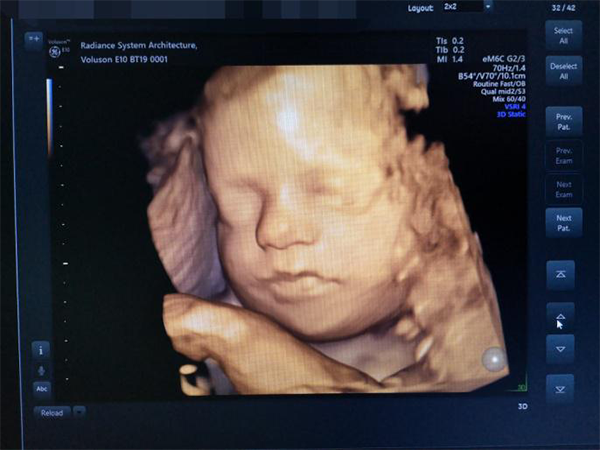

女性怀孕后,生男生女一直是人们比较关注的话题,四维彩超怎么分辨男孩女孩网传很多版本。四维彩超一般在怀孕24~28周的时候进行检测,这是宝宝的生殖器官已经生成,并且四维可以观察宝宝在子宫内的动态图像,自然也就能准确判断胎儿性别。

四维彩超可以看到胎儿的生殖器官

1秘诀一:四维彩超单子上,顶头最右边有两行字,是英文字母和数字组成的,第一行是日期,第二行是时间,如果第一行是M开头,那就是male男,表示生男孩;如果是F开头就是female女,表示生女孩。2秘诀二:四维彩超单子上有英文字母,但不是每一张都会有,得到孕妈的运气了。彩超单上很小英文字母Qual high 1是女孩,表示怀的女宝;2是男孩,表示怀的男宝。3秘诀三:四维彩超单子上,看胎儿宝宝外生殖器官特征,女孩一般是三条白线,两腿中间有小凹槽;男孩一般是亮点,两腿中间有小突起。4秘诀四:四维彩超单子,看结果是否双肾分离,如果显示“双侧肾盂分离”,那90%是男孩,因为男胎儿一般都有憋尿的习惯;如果是“双侧肾盂未见明显分离”,那95%是女孩。

已生女儿的四维彩超单子分享